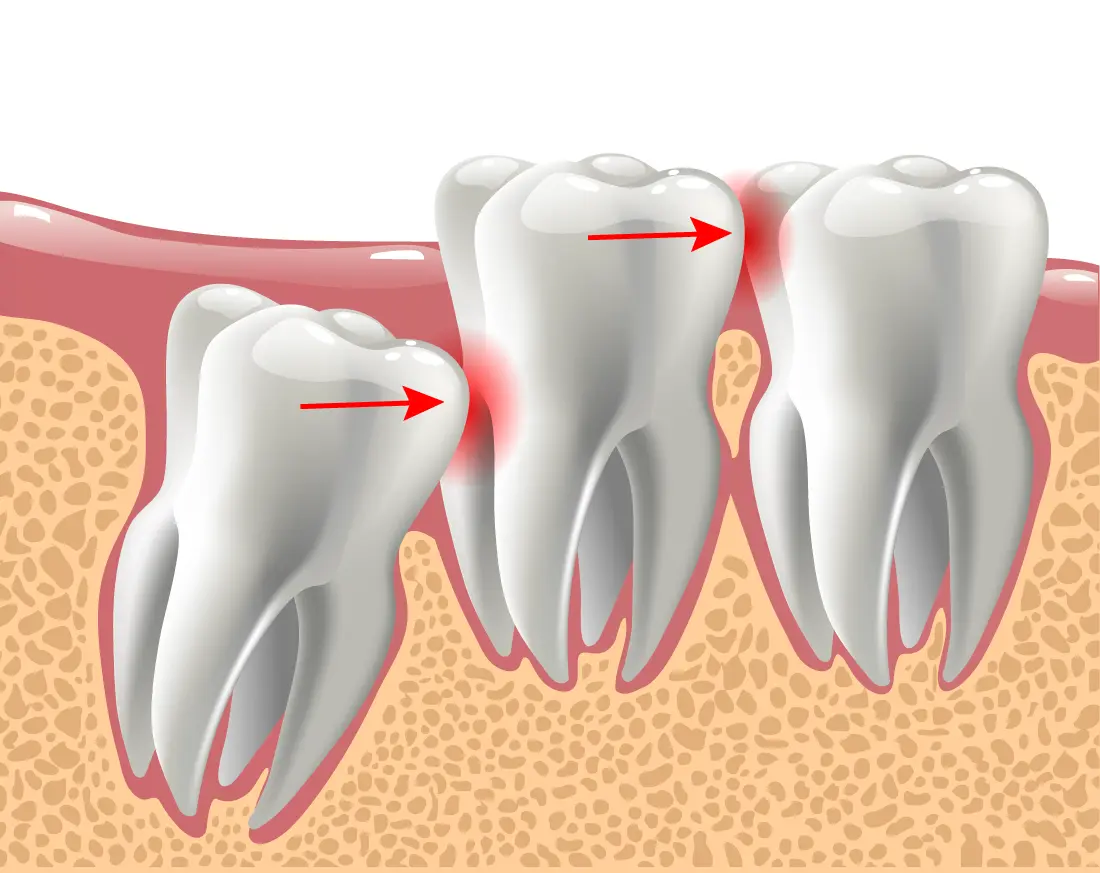

Wisdom Teeth Removal

Wisdom teeth removal may be the most common oral surgical procedure, but it can be a complicated one. That's why it's important to go to an expert. Our doctor specializes in complex issues of the teeth and mouth so you can rest assured knowing your teeth are in expert hands.